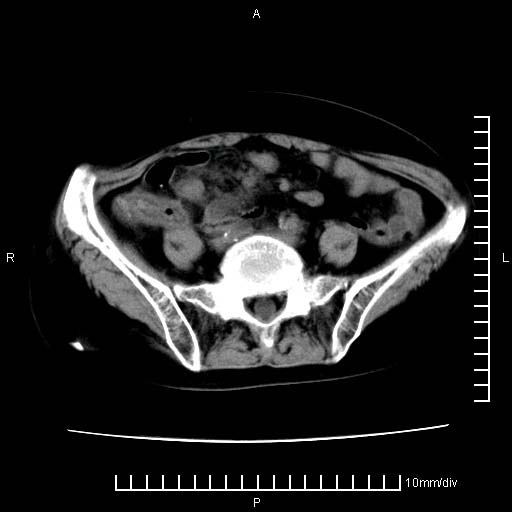

下腹疼痛2月,加重并呕吐2天,下腹压痛,反跳痛。白细胞1万2.

下腹至盆腔较大包块,与邻近肠管关系密切,下腹疼痛2月,加重并呕吐2天,下腹压痛,反跳痛。白细胞1万2.

由于没有做肠道准备很难分清是哪根肠管,但看位置考虑为升结肠回盲部的问题,我首先考虑化脓性阑尾炎,不除外结肠癌合并感染化脓。建议做增强进一步明确。

补充:道格拉斯腔内有积液,且密度较高,显然提示有感染。

考虑右侧卵巢囊肿伴感染可能性大。

附件实性肿块有坏死 考虑卵巢癌

来源于附件占位—多考虑:卵巢癌!